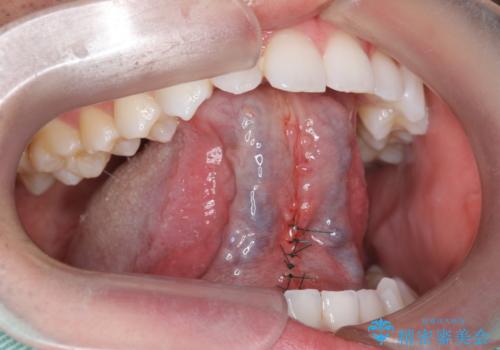

- 舌小帯の切除を希望して来院。

口を大きく開けた時に、上顎に舌がつかない状態でした。